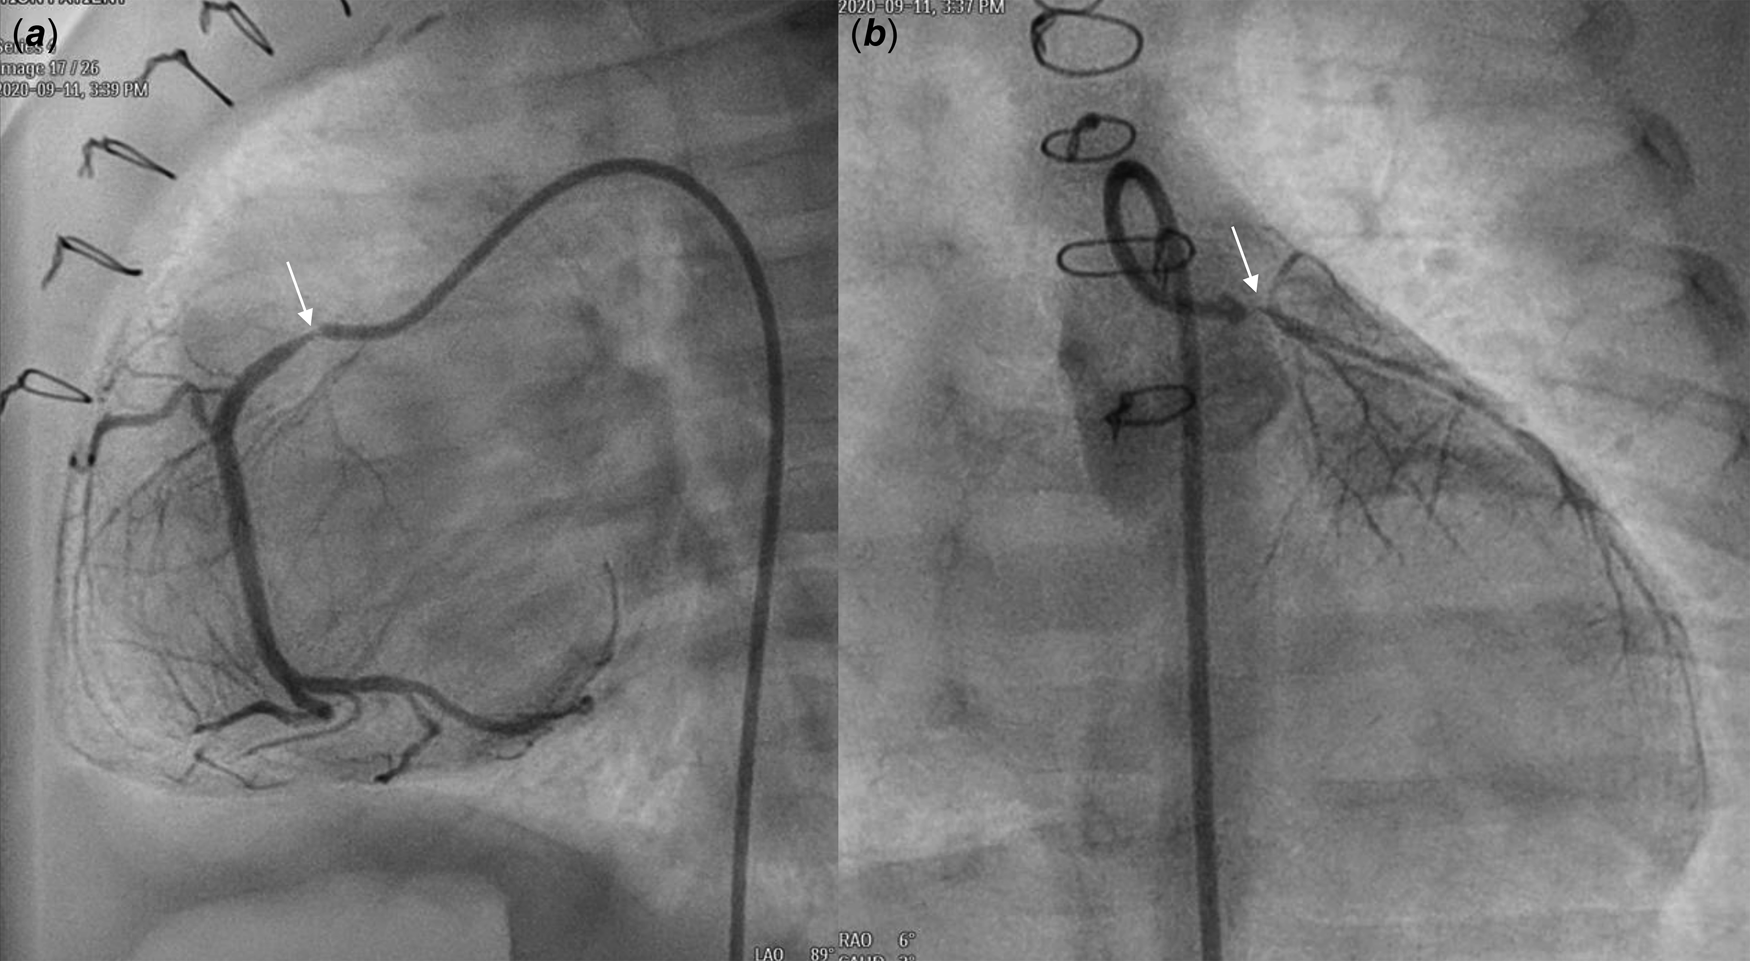

A male patient with d-transposition of the great arteries with an intact ventricular septum underwent arterial switch operation at 7 days of age. He had abnormal coronary arteries, both arising from a single coronary sinus, and an unusual left coronary artery with an intramural course. Both coronary arteries were re-implanted successfully by unroofing the left coronary artery ostium. One month after arterial switch operation, he presented to the emergency department with severe left ventricular dysfunction (left ventricle ejection fraction = 20%) and heart failure. Urgent coronary angiography confirmed severe stenosis of the proximal right coronary artery (Fig 1a) and near total occlusion of the left coronary artery ostium (Fig 1b). Emergent angioplasty of the left coronary artery ostium was performed in the 5-kg-body-weight patient. After post-operative recovery and improvement of left ventricular function, ventricular dysfunction (ejection fraction = 15%) re-developed at 4 months of age, approximately 2 months after the second operation. Percutaneous coronary intervention was planned in the infant, now 7 kg of body weight, to be performed by a paediatric cardiologist and adult interventional cardiologist. Elective extracorporeal membrane oxygenation of the right internal jugular vein-right common carotid artery was performed before percutaneous coronary intervention. Coronary angiography showed 95% segmental stenosis of the left coronary artery and 99% diffuse stenosis of the right coronary artery. Left coronary artery angioplasty with a 2.0 × 15-mm Maverick balloon was conducted successfully at 8 atm (Fig 2a), and 30% residual stenosis without dissection was confirmed (Fig 2b). Due to the unusual position of the right coronary artery, a 5-Fr JR 4.0 guiding catheter was reshaped and engaged properly with the right coronary artery. Runthrough and Sion guidewires were used to cross the lesion. Because 50% residual stenosis was found in the right coronary artery after angioplasty with 2.0 × 15-mm Maverick balloon at 12 atm, stent implantation with a 2.25 × 26-mm Orsiro stent at 12 atm was performed successfully (Fig 2c). After post-adjunctive balloon dilatation with 2.5 × 8-mm NC balloon, 10% residual stenosis in the right coronary artery was confirmed without dissection (Fig 2d). The total fluoroscopy time was 85 minutes. The patient was weaned successfully from extracorporeal membrane oxygenation the next day. Echocardiography at 7 days after percutaneous coronary intervention showed recovered ventricular contraction (left ventricle ejection fraction = 60%) but dilated left ventricle. The patient’s symptoms were relieved, and he was discharged on dual antiplatelet therapy with aspirin and clopidogrel. No complications related to femoral arterial cannulation in such a small patient were detected.

Figure 2. Coronary angiography after PCI showed balloon angioplasty (thick arrow) for LCA stenosis ( a ) with mild residual stenosis ( b ) and stent implantation (blank arrow) for RCA severe stenosis ( c ) with minimal residual stenosis ( d ). PCI: percutaneous coronary intervention, LCA: left coronary artery, RCA: right coronary artery.